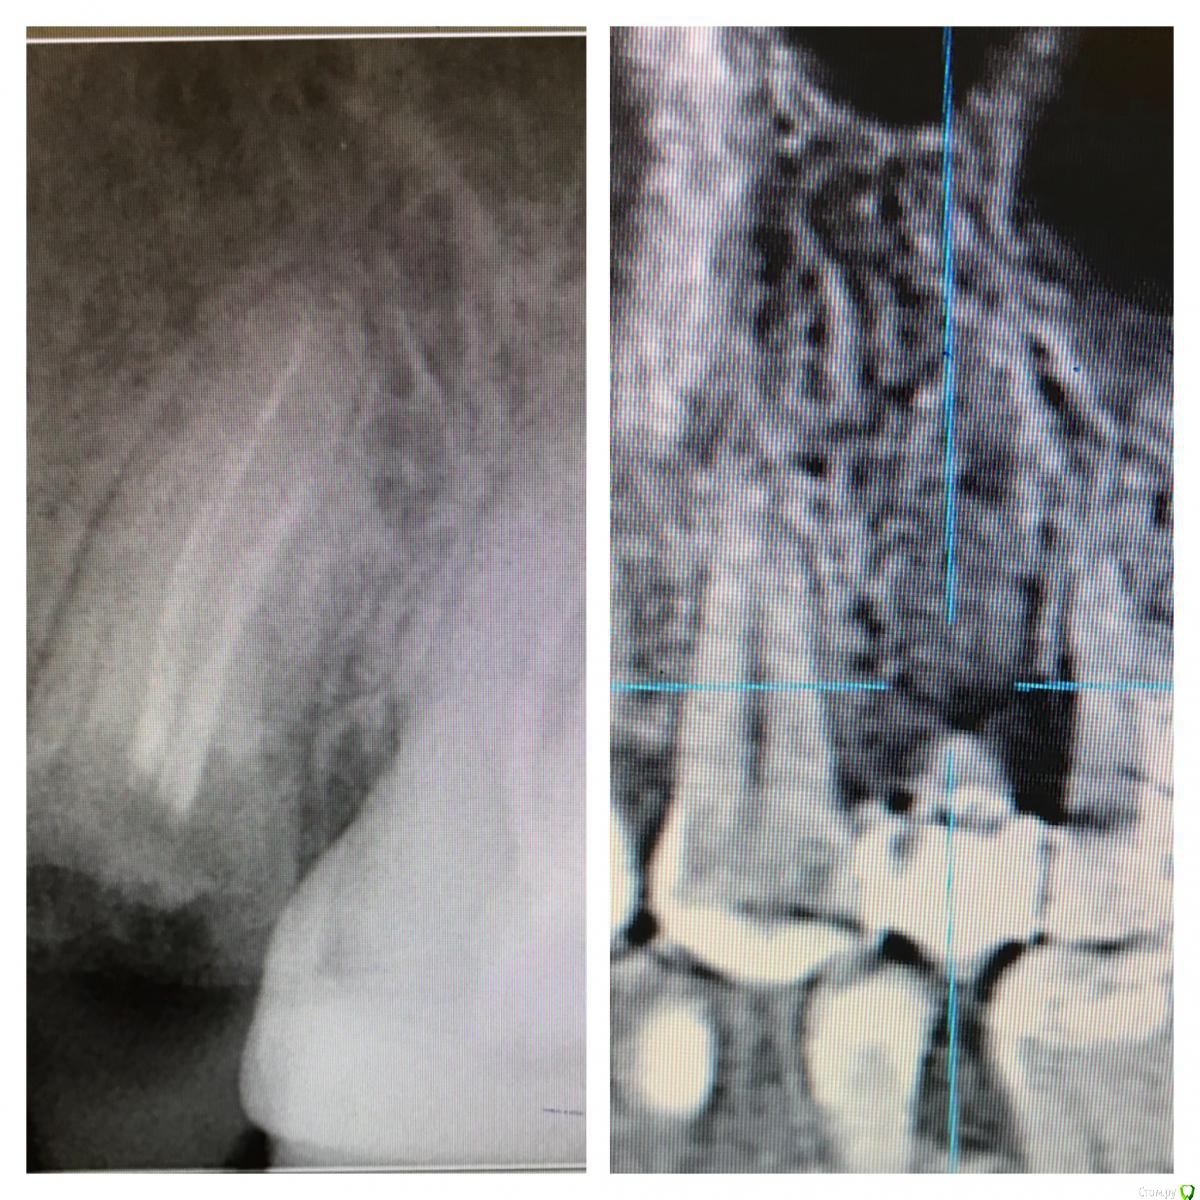

Astronaft Опубликовано 6 июля, 2018 Поделиться Опубликовано 6 июля, 2018 (изменено) Я пробовал один раз.Впечатления смешанные.1. просто в исполнении.2. Хорошо, быстро заживает. Есть ощущение что так можно проводить профилактику альвеолита.3 .Десны действительно достаточо.4. Кость - неоднозначно. Надо попробовать 2 рядом стоящих зуба "с шайбой" и "без".5. Шайба удаляется легко. Без анестетика, зондом поддел.6. Поверхность под шайбой - белая соед.тканная пленка. Рентген в день удаления -> фото через неделю -> фото через 2 месяца + КЛКТ ( срезы: перегородка и оба корня) http://miworks.weebly.com/uploads/1/6/8/7/16879370/x07221.jpg http://miworks.weebly.com/uploads/1/6/8/7/16879370/dscn6666_orig.jpg http://miworks.weebly.com/uploads/1/6/8/7/16879370/dscn6948_orig.jpg http://miworks.weebly.com/uploads/1/6/8/7/16879370/dscn6943_orig.jpg http://miworks.weebly.com/uploads/1/6/8/7/16879370/dscn6952_orig.jpg http://miworks.weebly.com/uploads/1/6/8/7/16879370/dscn6953.jpg http://miworks.weebly.com/uploads/1/6/8/7/16879370/dscn6954.jpg http://miworks.weebly.com/uploads/1/6/8/7/16879370/dscn6949_orig.jpg http://miworks.weebly.com/uploads/1/6/8/7/16879370/x07221-1.jpghttp://miworks.weebly.com/uploads/1/6/8/7/16879370/x07221-4.jpg http://miworks.weebly.com/uploads/1/6/8/7/16879370/x07221-2.jpghttp://miworks.weebly.com/uploads/1/6/8/7/16879370/x07221-3.jpg Изменено 6 июля, 2018 пользователем Astronaft 4 Ссылка на комментарий

kamranchick Опубликовано 6 июля, 2018 Поделиться Опубликовано 6 июля, 2018 Я думаю если аккуратно удалить зуб, похожий результат будет(Ну по моим наблюдениям.У Вас Астронафт мне кажется также наверное все бы восстановилось бы, судя по первому прицельному RVG 1 Ссылка на комментарий